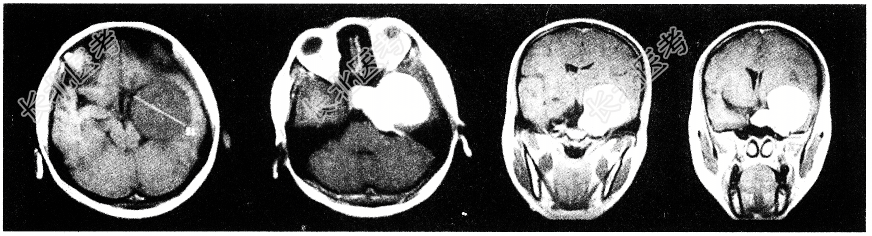

- 单项选择题女性患者,36岁。抽搐半年, 近10余天头痛加重,磁共振检查如图, 选择最可能的诊断

A、脑膜瘤

B、海绵状血管瘤

C、胶质瘤

D、蛛网膜囊肿

E、动静脉畸形